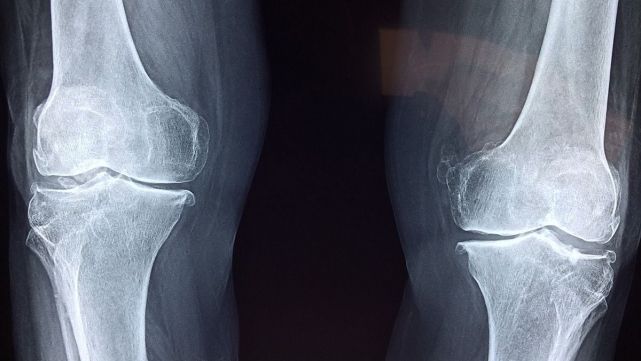

The injuries of knee more common

Breaks of meniscuss

The breaks of meniscus are used to to produce when the knees suffer impacts of high intensity, like sports maratonianos, football, basketball, etc. The meniscuss are structures that help to cushion the load exerted in the knee, between the bone femur and the tibia. Thus, his wear translates in breaks.